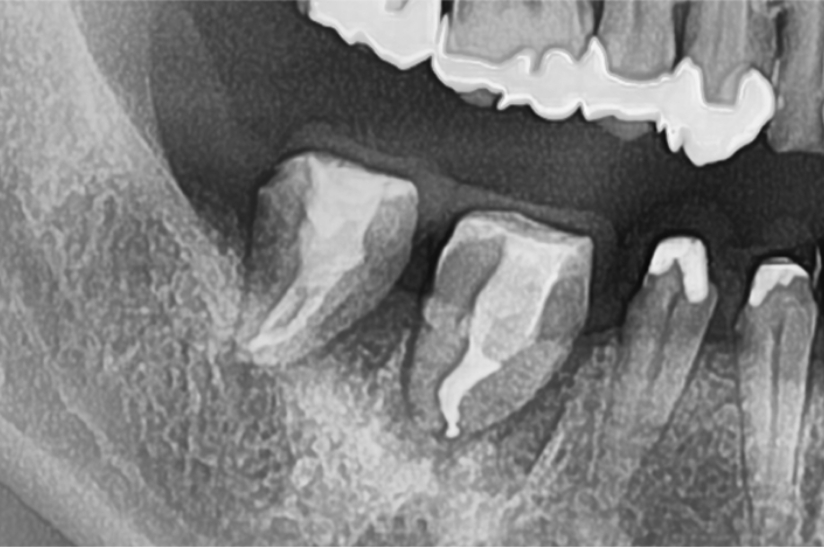

自家歯牙移植と根管治療で

天然歯を保存した症例

タップで写真の拡大ができます。

Before

Under Treatment

After

主訴

歯を残せないと言われた。インプラントは先延ばしにしたい

治療内容

自家歯牙移植 / イニシャルトリートメント(大臼歯)レジンコア

治療期間

2ヶ月

治療費用

308,000

治療の

リスク

術後しばらくしてから骨性癒着、外部吸収を起こす可能性があります。